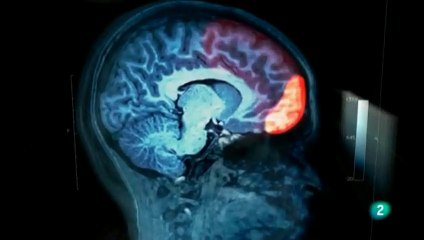

Varios son los modelos que se han aplicado para el fenómeno del uso compulsivo de drogas, pero desde el punto de vista de la neuropsicología dicho problema puede ser descrito como una condición asociada a la disfunción de mecanismos cerebrales que intervienen en la capacidad de tomar decisiones. Así, en los drogadictos, se considera que esta capacidad similar a la observada en los pacientes con lesiones de la corteza prefrontal ventromedial y orbitofrontal (CPVO), caracterizados por una marcada falta de memoria para las consecuencias a largo plazo de sus decisiones, y la imposibilidad de aprender de los errores repetidos. Estos pacientes tienden elegir la recompensa inmediata, a pesar de las consecuencias futuras negativas graves. Así, los individuos drogadictos comparten con pacientes con lesiones de la CPVO un cierto grado "de miopía" para el futuro.